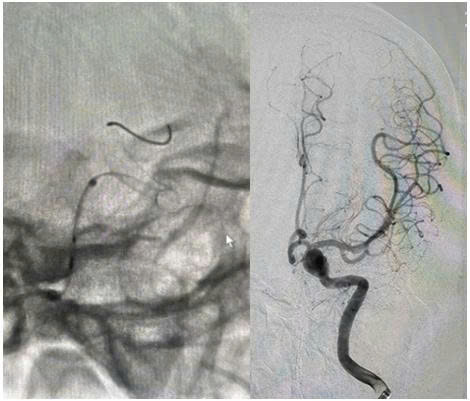

Ngay khi nhập viện, các bác sỹ nghi ngờ bệnh nhân có bất thường hệ thống mạch máu não nên đã chỉ định chụp cắt lớp vi tính mạch máu não cho bệnh nhân. Kết quả hình ảnh chụp cắt lớp vi tính mạch máu não cho thấy, bệnh nhân có túi phình lớn ở động mạch cảnh trong trái, kích thước khoảng 10 x 8 x 6 mm, khu trú tại đoạn động mạch mắt.

Hình ảnh túi phình lớn ở động mạch cảnh trong trái trên CLVT mạch máu não

Quá trình can thiệp được thực hiện qua động mạch đùi phải theo phương pháp Seldinger. Bệnh nhân được chụp mạch não để đánh giá chính xác túi phình. Ê-kíp đã đặt thành công stent chuyển dòng kích thước 4,25 × 20 mm qua cổ túi phình động mạch cảnh trong trái đoạn động mạch mắt. Hình ảnh sau can thiệp cho thấy stent áp sát thành mạch, che phủ hoàn toàn cổ túi phình, giảm rõ rệt dòng máu vào túi phình, đồng thời đảm bảo tưới máu não tốt, tuần hoàn não trước đạt TICI 3.

Hình ảnh thả stent chuyển dòng túi phình lớn ở động mạch cảnh trong trái dưới DSA